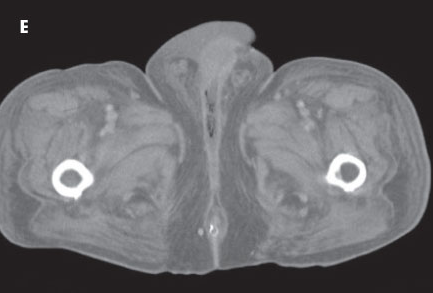

The follow-up CT scans of the abdomen and pelvis depicted dramatic improvement (E). The extraluminal gas had nearly resolved. The patient’s clinical course was ultimately favorable, and he was discharged.